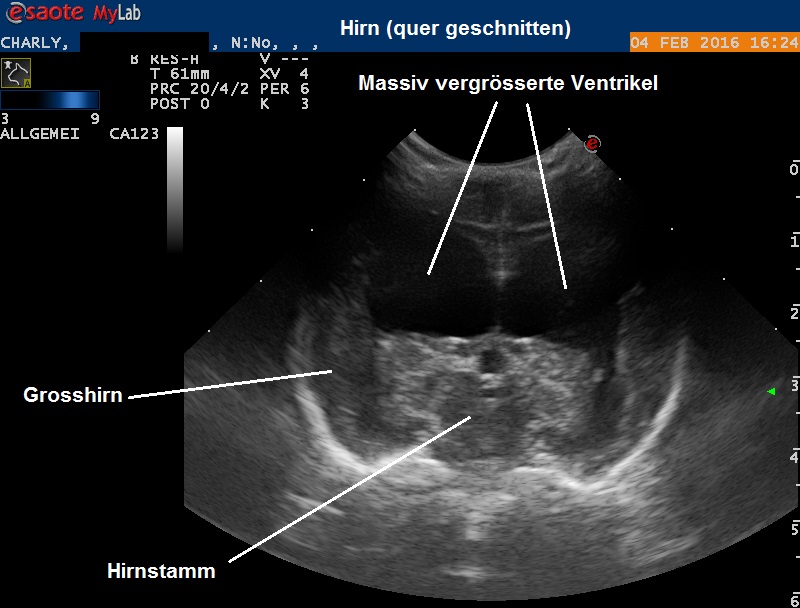

Das beobachtete Bild ist typisch für einen Hydrocephalus, einen "Wasserkopf". Zur Beweisführung wird ein Ultraschall angefertigt:

Durch die fehlende Knochenschicht aufgrund der offenen Fontanelle kann das Hirn problemlos mittels Ultraschall untersucht werden - im Normalfall wäre dies unmöglich, weil Knochen den Ultraschall reflektiert. Es ist sehr deutlich zu erkennen, dass das Hirn eine sehr grosse Menge an Flüssigkeit enthält - die normalerweise nur geringste Mengen an Liquor (Nervenwasser) enthaltenen Ventrikel sind stark aufgebläht, das Hirngewebe wird dadurch stark komprimiert und ist deutlich weniger umfangreich als normal.